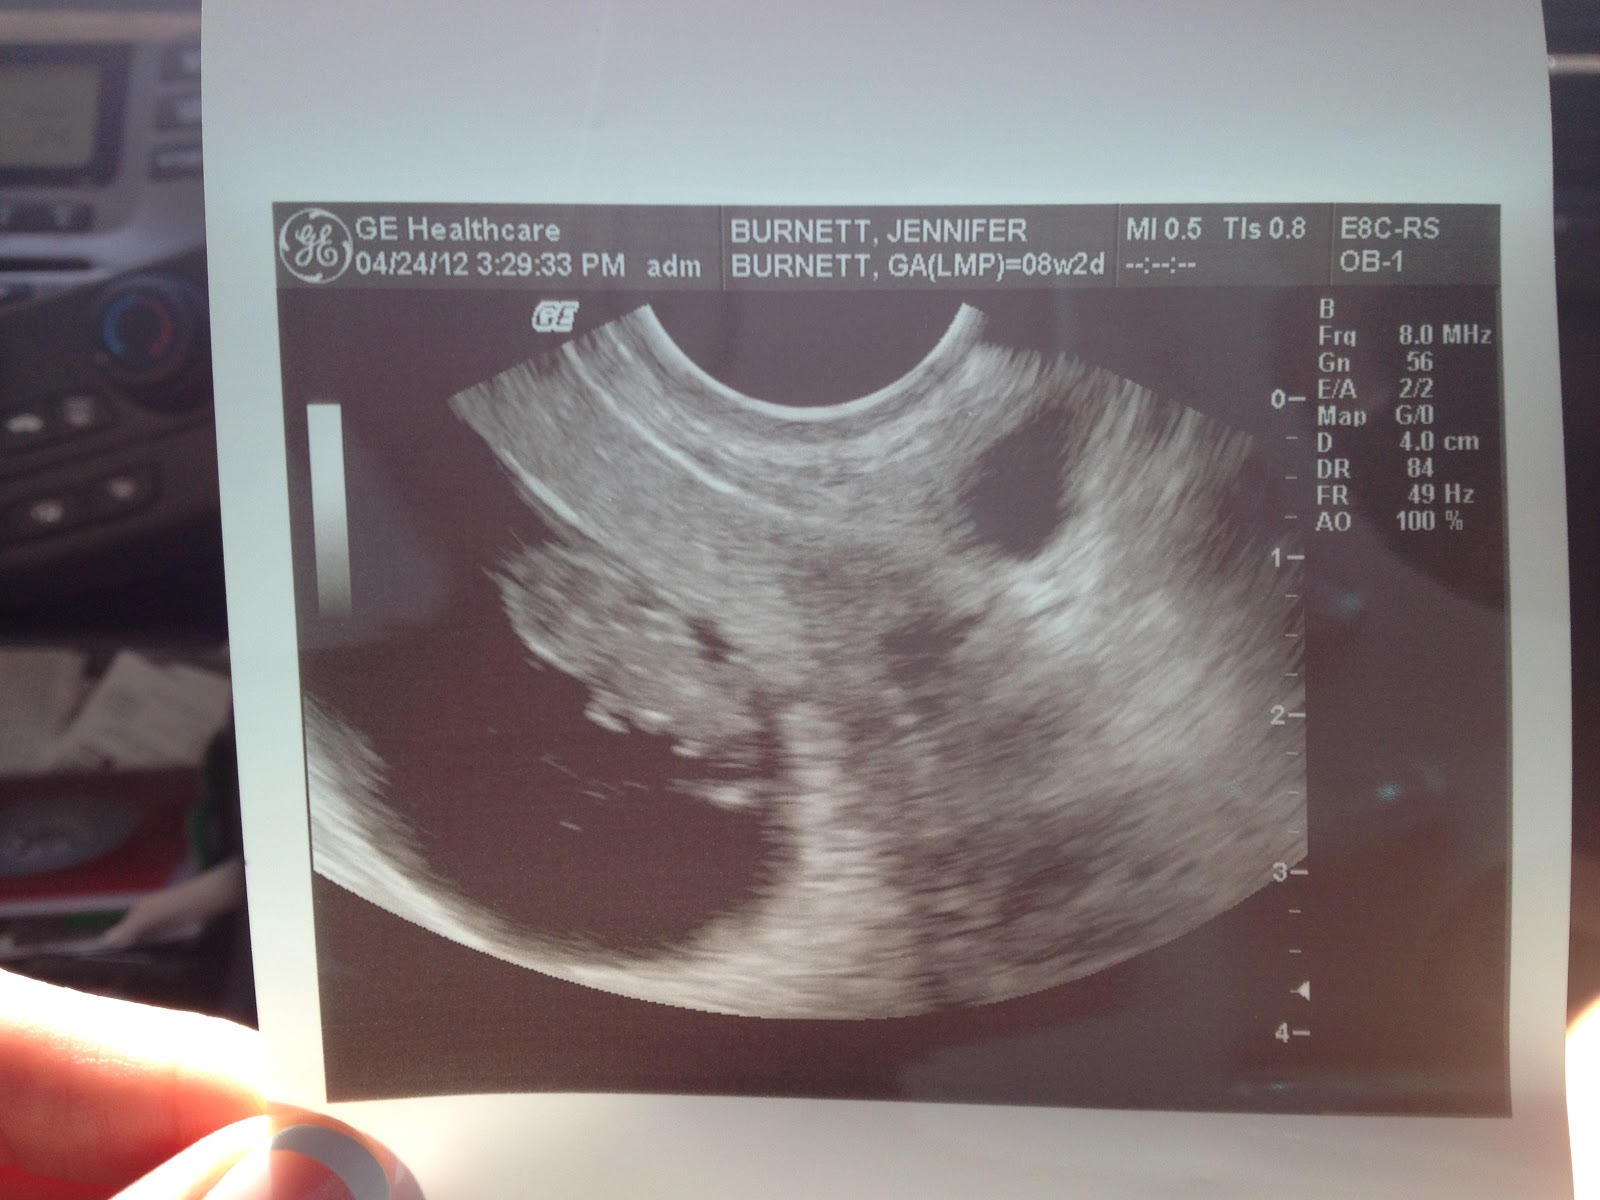

I started the online research and found out the estimated due date 12/3/12. We decided he would tell his parents and I would call mine that day. Lots of initial shock… We might still be adjusting to it.